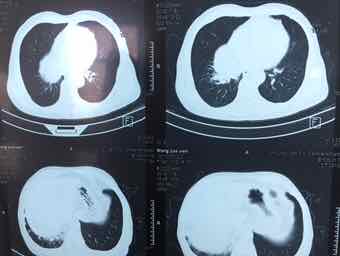

男,74岁,咳嗽咳痰3个月,无发热,无胸痛,无盗汗,无咳血。右肺占位性质待查?完善气管镜检查